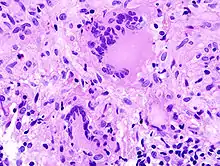

• TOUTON-Riesenzelle - Schaumzellen, bei denen um eine kleine schaumfreie Insel mehrere Kerne ringförmig angeordnet sind, Vorkommen z.B. bei juveniler Xanthogranulomatose, siehe Abb.

• Riesenzelle bei Epulis